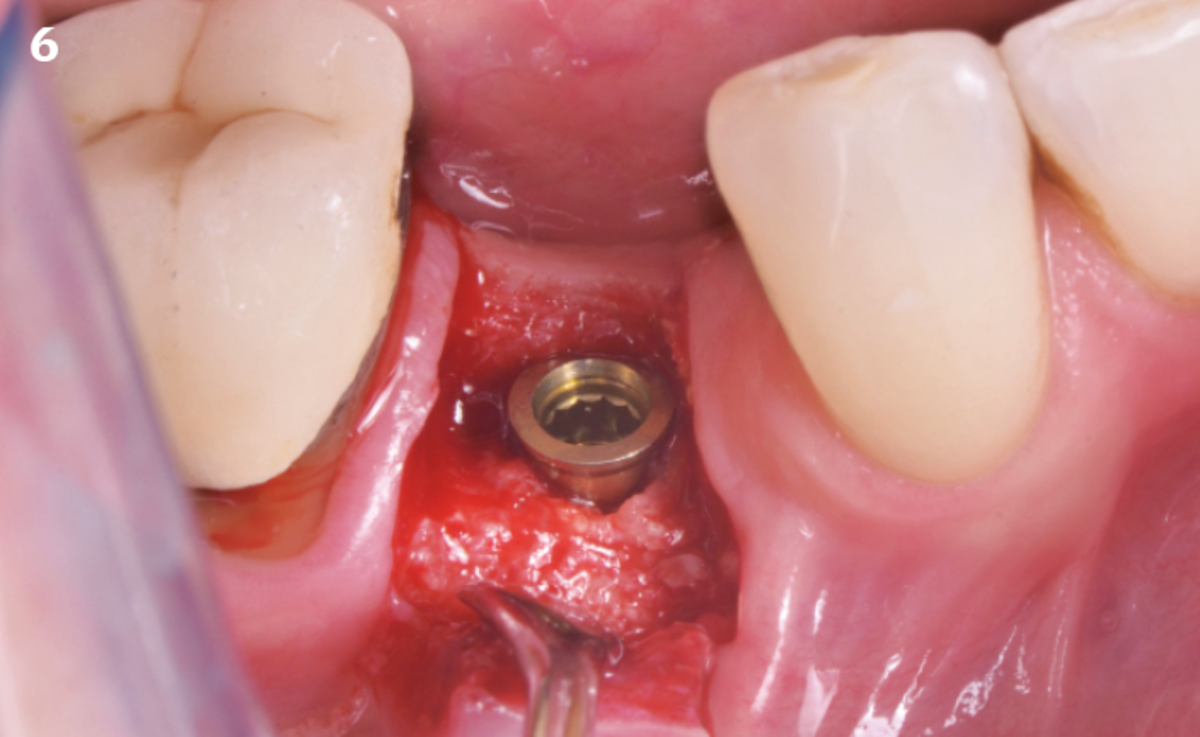

Extraction socket management with REGENFAST®

Ridge reconstruction before implant placement

The patient (45 years old, female, non-smoker, no previous pathologies) is referred for extraction of tooth 45 and immediate implant placement. The site showed an increased probing depth and a marked bone loss.